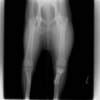

左後肢の挙上を主訴に来院されました。触診にて両関節の前方引き出し兆候、両膝蓋骨の内方脱臼を認めました。関節液検査より免疫介在性多発性関節炎は否定的でした。レントゲン検査にてfat pad signを伴う関節炎が認められたことから、前十字靭帯断裂と膝蓋骨内方脱臼(左GradeⅢ 右GradeⅢ〜IV)併発と診断し、手術を行いました。

術前正面像

術前のTPAは左後肢33.1°右後肢26.8°でしたがTPLO実施により左後肢5.5°右後肢12°に矯正されました。